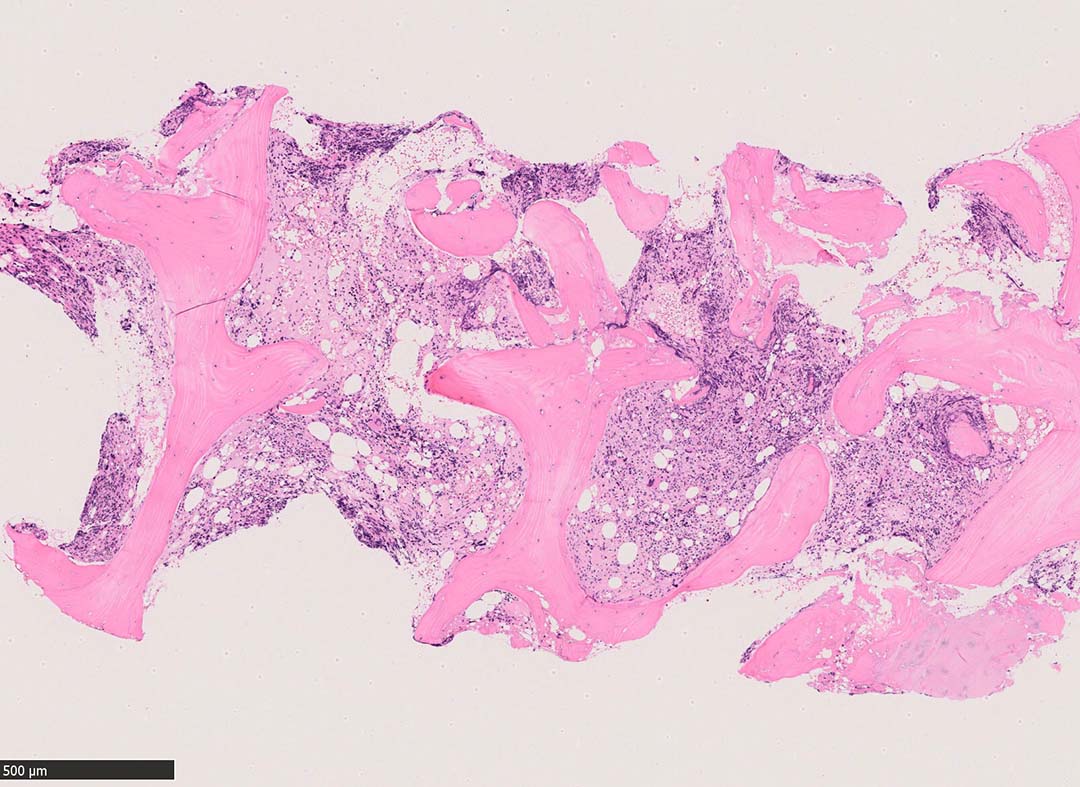

Case02; Meylofibrosis, overt fibrosis

77year-old female. 40歳時polycythemia veraと診断されていた.

[注] この症例は詳細は不明であるが, 過去にPVと診断されているため, PVに伴う二次性のmyelofibrosisの診断になる.

黒染する弾性線維の増生のほか, 赤く染まる膠原線維の増生が確認される. MF-2 fibrosis. 鍍銀染色の核染色をすると膠原線維の赤染がわからなくなるので行わない.